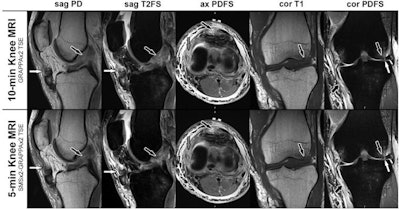

MRI scans in a 28-year-old man with a left knee injury from playing soccer. The corresponding noncontrast axial, sagittal, and coronal MRI scans of the 10-minute parallel imaging-accelerated knee MRI protocol (upper row) and five-minute simultaneous multislice- and parallel-accelerated knee MRI protocol (lower row) were obtained at 1.5-tesla field strength. Sagittal proton density-weighted (sag PD) and sagittal T2-weighted fat-suppressed (sag T2FS) MRI scans demonstrate a tear of the anterior cruciate ligament (black arrows) and a patella tendon tear (white arrows). Axial proton density-weighted fat-suppressed (ax PDFS) MRI scans redemonstrate the patella tendon tear (black arrows) and a tear of the medial collateral ligament (gray arrows). Coronal T1-weighted (cor T1) MRI scans demonstrate a bone contusion of the lateral femoral condyle with small, nondisplaced subchondral fracture (arrows). Coronal proton density-weighted fat-suppressed (cor PDFS) MRI scans redemonstrate the medial collateral ligament tear (short black arrows), a tear of the lateral meniscus (white arrows), and subchondral bone marrow edema pattern (long black arrows). Image courtesy of Radiology.These findings suggest that rapid knee MRI is within reach, according to a commentary that accompanied the study.